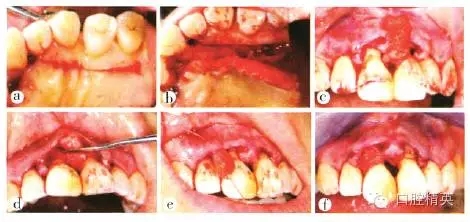

a 2112唇側(cè)做溝內(nèi)切口;b 腭側(cè)做半月形切口,保留齦乳頭;c 將齦乳頭自腭側(cè)完整翻至唇側(cè);d 切口腭側(cè)觀

圖5 牙周膜齦手術(shù)切口

a 自23456腭側(cè)齦緣根方3 mm相應(yīng)處做水平切口;b 制備帶蒂結(jié)締組織瓣,長25 mm、寬10mm,蒂部與幢腭側(cè)軟組織相連;c 通過11牙間隙將帶蒂組織瓣自腭側(cè)翻卷至唇側(cè);d 將帶蒂組織瓣同定于唇側(cè)齦瓣組織面.增厚齦乳頭;e 將截取的游離結(jié)締組織瓣置于21之間;f 固定組織瓣于21間齦乳頭下方組織面

圖6 軟組織移植

a松弛211唇側(cè)齦瓣,冠向懸吊并以流動樹脂固定線結(jié)于11冠中1/3處,2112齦乳頭間斷縫合;b腭側(cè)觀;c供區(qū)鎖扣式縫合

圖7 術(shù)后縫合